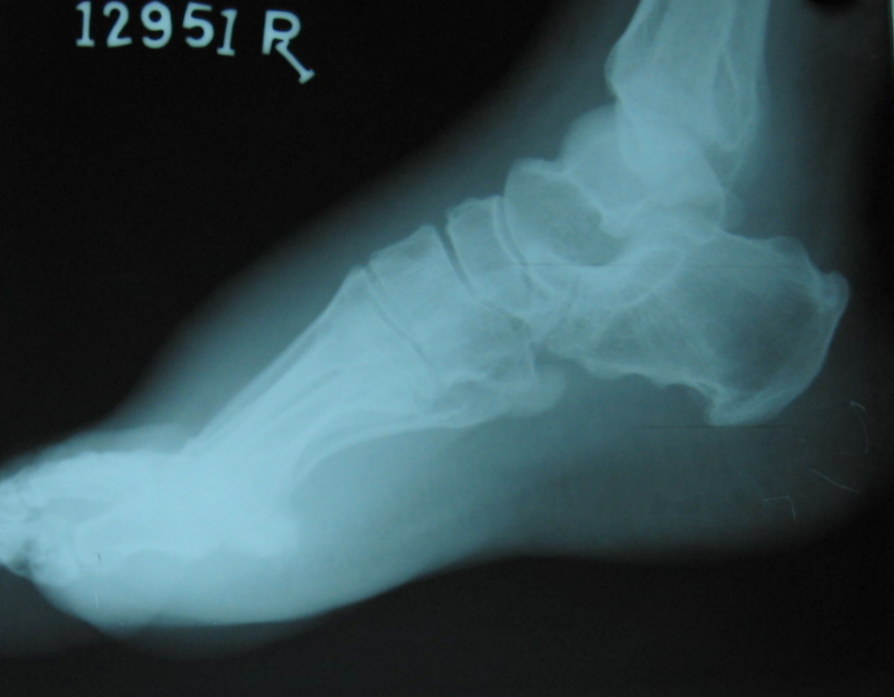

acromegaly foot NEW